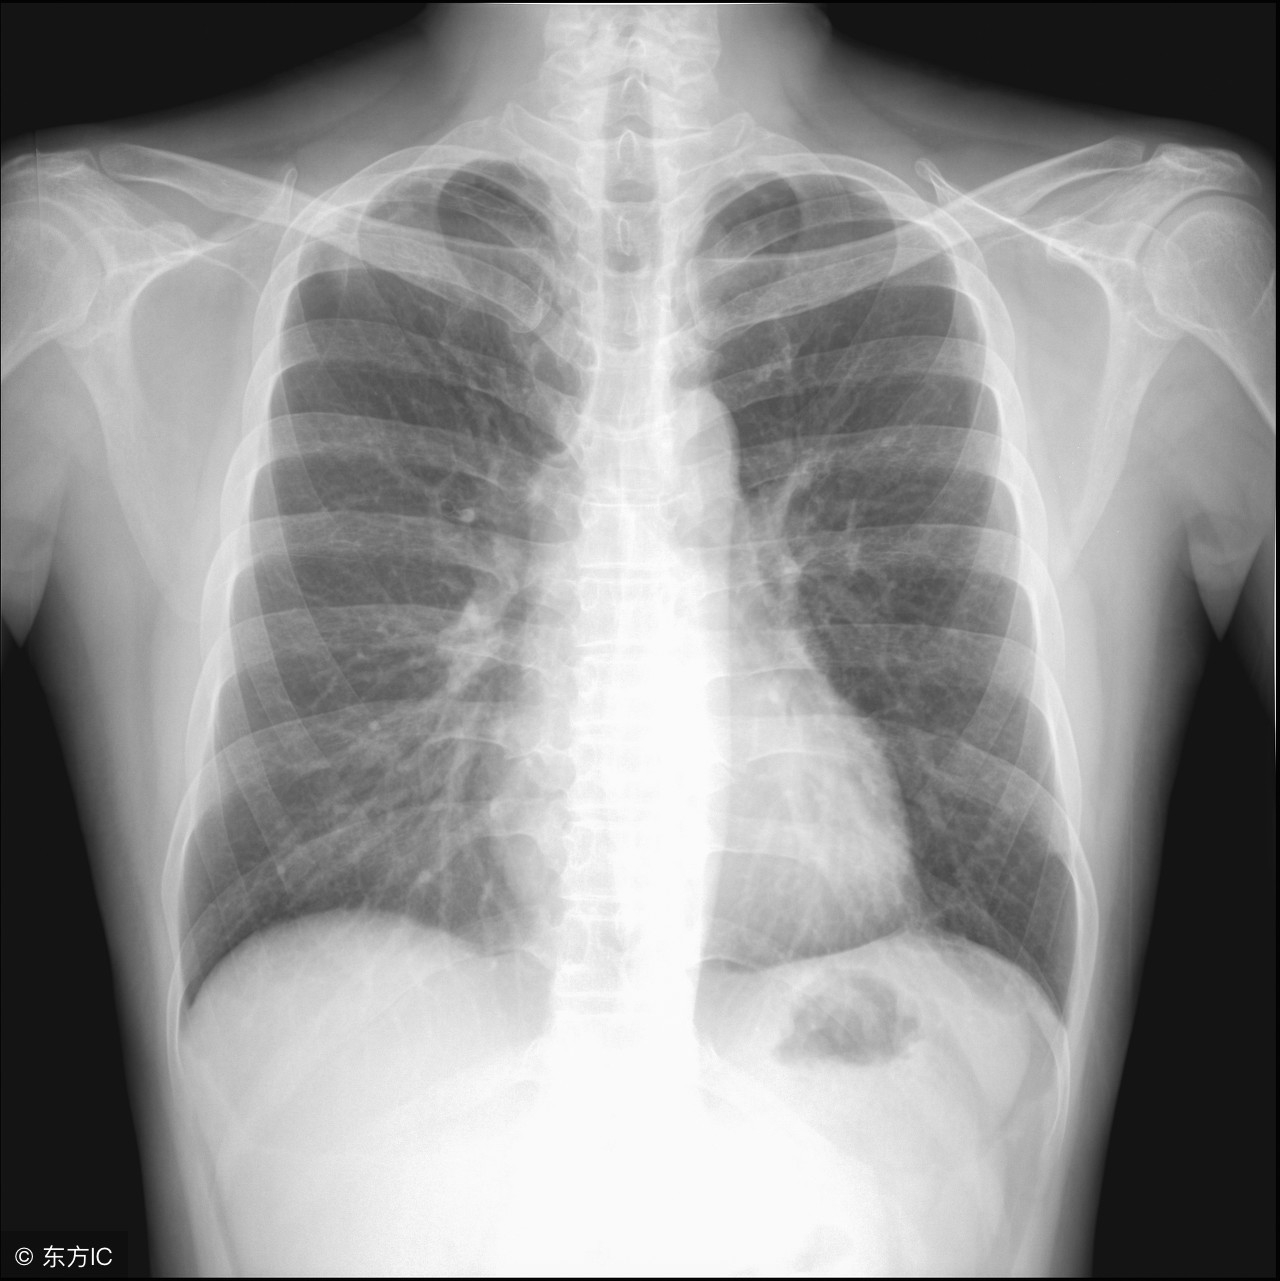

什么是肺大疱?肺大疱又称肺大泡,指的是由于某些特殊的因素,例如患者体内肺泡的腔内的内外压力不一致,也就是内部压力过高导致用来保护肺泡内部结构的肺泡壁被直接损坏,即涨破,从而在患者的肺部形成了新的物质、组织或者结构等的一种疾病。这种疾病分先天性的和后天性的,前者一般是出现的人群以小孩子为主,而后者则是那些已经成年的人并且多见于老年人。

患有肺大泡时,一般在没出现症状或者问题前人们是不会采取措施的,一般都是在出现症状时候才进行治疗的。其实这种疾病并不像癌症那般很难治疗,但是及时发现还是很有必要的。要想解决肺大泡带来的气胸问题,关键还是解决源头,也就是患者体内的肺大泡。

目前世界上治疗肺大泡的方式很多,但是医院一般会采取相对比较安全的方式,即胸腔镜肺大泡切除手术,这种手术实施起来并不是很困难,并且手术风险很低,对患者的身体造成的伤害很小并且患者在手术之后可以恢复得很快。